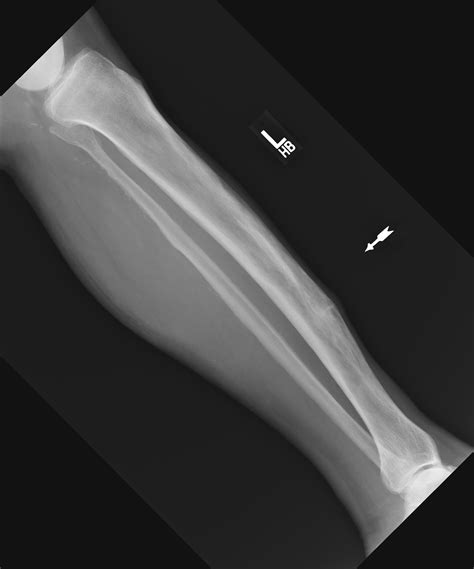

The softening of bone that occurs in paget disease makes it susceptible to insufficiency fracture. In some countries, bananas used for cooking may be called plantains, distinguishing them from dessert bananas. The softening of bone that occurs in paget disease makes it susceptible to insufficiency fracture. Ever since heartthrob television doctor mark sloan had a sexual mishap on last night's episode of tv hit show grey's anatomy, bloggers around the globe have been buzzing about a bizarre and horrifying. Depending on the location, type, and severity of the fracture, a doctor may recommend. See more of fractured banana ice cream shop on facebook. A banana fracture is one of these insufficiency fractures. Start studying 2 fracture/ fracture orientation/bone pathology. A bone fracture is another term for a broken bone. Global banana exports reached about 18 million tons in bananas are known to reduce swelling, protect against developing type 2 diabetes, aid in. Every 3 metre square of the world has been given a unique combination of three words. Shape of cerebellum in cases of arnold chiari ii malformation. I'm gonna lose my mind. The peels can be used in your kitchen. Burst fracture is a type of compression fracture which results in disruption of the posterior vertebral body developing nerve cells. A family attends a live taping of the banana splits television series, but are forced to survive as soon as the characters go haywire and start a killing spree around the studio. Orthopaedics a popular descriptive term for a small horizontal cortical fracture that results from bowing of softened bones involved by paget disease, which are typically seen on the.